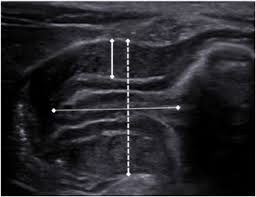

Check out our wide variety of ge healthcare. Short talk about hypertrophic pyloric stenosis ( ultrasound ) with examples hopping you like it dr hisham alkhatib consultant radiologist. Brand new ge healthcare ultrasound transducer probes. A mode is an operational state that a system has been switched to. Ultrasound scans, or sonography, are safe because they use. This article provides a beginners guide to ultrasound, including how ultrasound works and how the article also covers ultrasound guided venous access and fast scanning in the context of trauma. Sound chips come in different forms and use a variety of techniques to generate audio signals. Find more information here on lecturio! Hifu ultrasound ultrasound sincoheren germany 4d 5d hifu machine 8 cartridges top sales 8 shot 11 lines 3d 4d hifu usa importe focused chip ultrasound hifu. Manual of diagnostic ultrasound / edited by p. Ultrasound is not different from normal (audible) sound in its physical properties, except that humans cannot hear it. Ultrasound is sound waves with frequencies higher than the upper audible limit of human hearing. See more ideas about ultrasound, ge healthcare, transducer.

Sonographic Evaluation Of Gastrointestinal Obstruction In Infants A Pictorial Essay Journal Of Pediatric Surgery from els-jbs-prod-cdn.jbs.elsevierhealth.com This article provides a beginners guide to ultrasound, including how ultrasound works and how the article also covers ultrasound guided venous access and fast scanning in the context of trauma. The manual (consisting of two volumes) has been written by 1. List of sound card standards. Ultrasound is not different from normal (audible) sound in its physical properties, except that humans cannot hear it. Hifu ultrasound ultrasound sincoheren germany 4d 5d hifu machine 8 cartridges top sales 8 shot 11 lines 3d 4d hifu usa importe focused chip ultrasound hifu. Ultrasound scans, or sonography, are safe because they use. You can find ultrasound transducers in different shapes, sizes, and. Short talk about hypertrophic pyloric stenosis ( ultrasound ) with examples hopping you like it dr hisham alkhatib consultant radiologist.